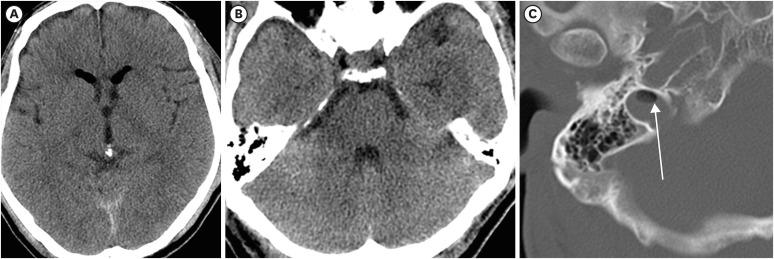

硬脑膜静脉窦血栓形成(DVST)和脑静脉梗死的发病率尚不完全清楚,但DVST与静脉窦周围的颅骨骨折密切相关。一名56岁男性被坠落的机器击中面部后出现大量水样分泌物。入院时他神志清醒,无脑脊液漏出。脑部计算机断层扫描显示颈静脉窝有空气密度影。外伤后第3天,他突然出现呼吸困难和意识丧失,陷入昏迷。脑部磁共振成像显示延髓、脑桥和右侧小脑半球急性水肿,右侧延髓局灶性梗死。脑血管造影显示乙状窦和颈静脉闭塞,右侧后颅窝静脉循环减少。窦内的空气密度影可能是发生静脉血栓形成的一个指标,颈静脉球周围的DVST可能继发脑干静脉梗死。